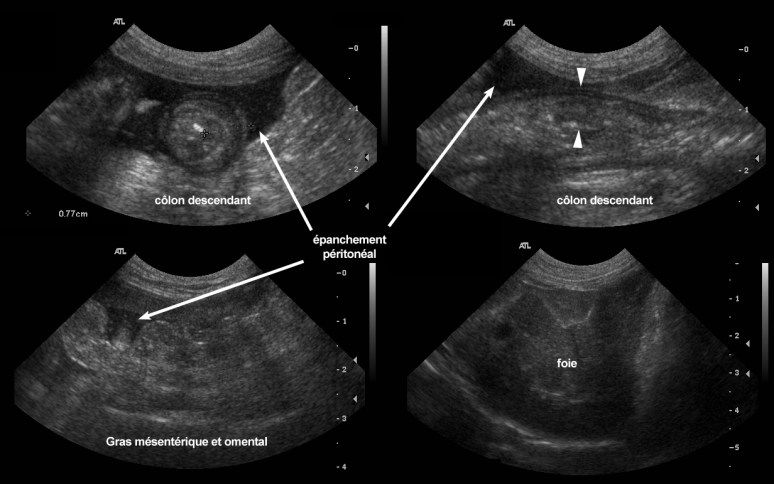

Celui-ci a confirmé la présence d’un épanchement péritonéal d’aspect granulaire (cellulaire) et un épaississement nodulaire et globalement hyperéchogène des gras mésentérique et omental. Le foie était aussi plus gros et diffusément hypoéchogène de façon homogène. Un épaississement de la paroi du côlon a aussi été identifié (jusqu’à 8mm, vs. 1-2mm) sur plus de 10 cm de longueur. Cet épaississement était asymétrique et associé à une altération des couches pariétales. Des noeuds lymphatiques coliques et jéjunaux étaient aussi augmentés de volume et hypoéchogènes. Un carcinome colonique avec carcinomatose péritonéale (i.e. dissémination et implantation de cellules cancéreuses) a été diagnostiqué par cytoponction échoguidée.